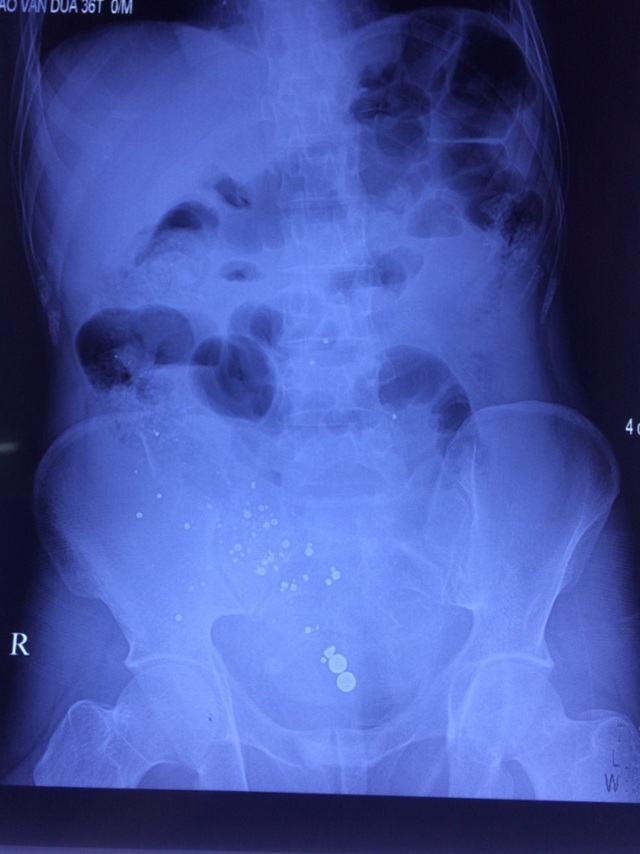

Nhiều dị vật đạn xuyên thấu bụng người bệnh do sung cướp cò.

Kết quả phim chụp cho thấy có nhiều dị vật cản quang ở trong ổ bụng. Ngay lập tức, bệnh nhân được mổ cấp cứu với chẩn đoán vết thương thấu bụng do hỏa khí.